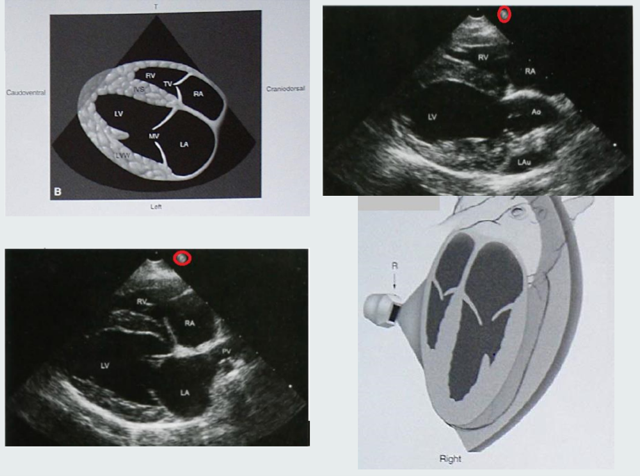

In longitudinal views, the base of the heart is…

In transverse images the pulmonary artery is…

A

In longitudinal views the base of the heart is towards the right side of the monitor and the apex to the left.

In transverse images the pulmonary artery is seen on the right side of the screen.

The reference mark on the transducer and the symbol on your screen: Whatever the reference mark is directed toward in the body during an exam will be seen on the side of the sector image of the symbol.

The standard protocol for cardiac imaging requires the reference symbols to be displayed on the right side of the sector image.

Describe Longitudinal view of the thoracic contents during U/S.

Use the 3rd to 6th intercostal space.

The transducer is close to the sternum in cats but further away in larger dogs.

The reference mark is cranially, towards the neck.

There is about 45°angle between the transducer and the animal.

The long axis is aligned from approximately shoulder to xiphoid.

(Short axis uses the same basic position as for the long axis view but rotate the transducer 90° towards the animals sternum.)